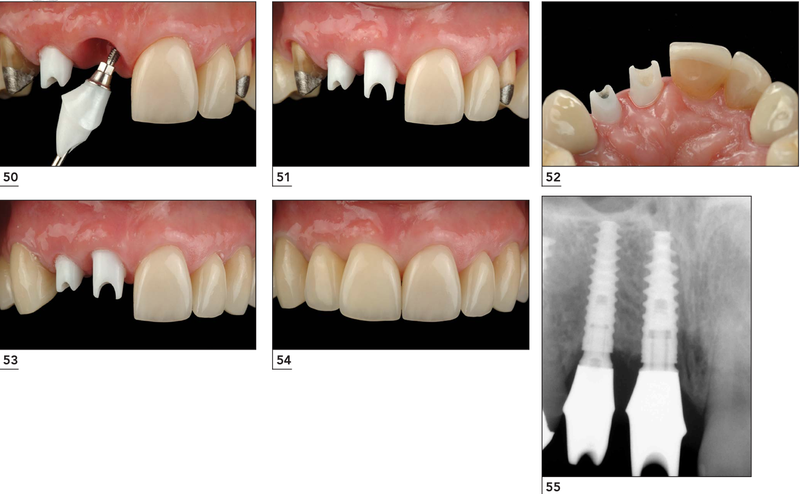

Hình ảnh trụ phục hình bán sẵn và giải phẫu cá nhân hòa bằng zirconia.

Trụ phục hình giải phẫu cá nhân hóa bằng Zirconia có hình dạng và màu sắc giống đúc thân răng.